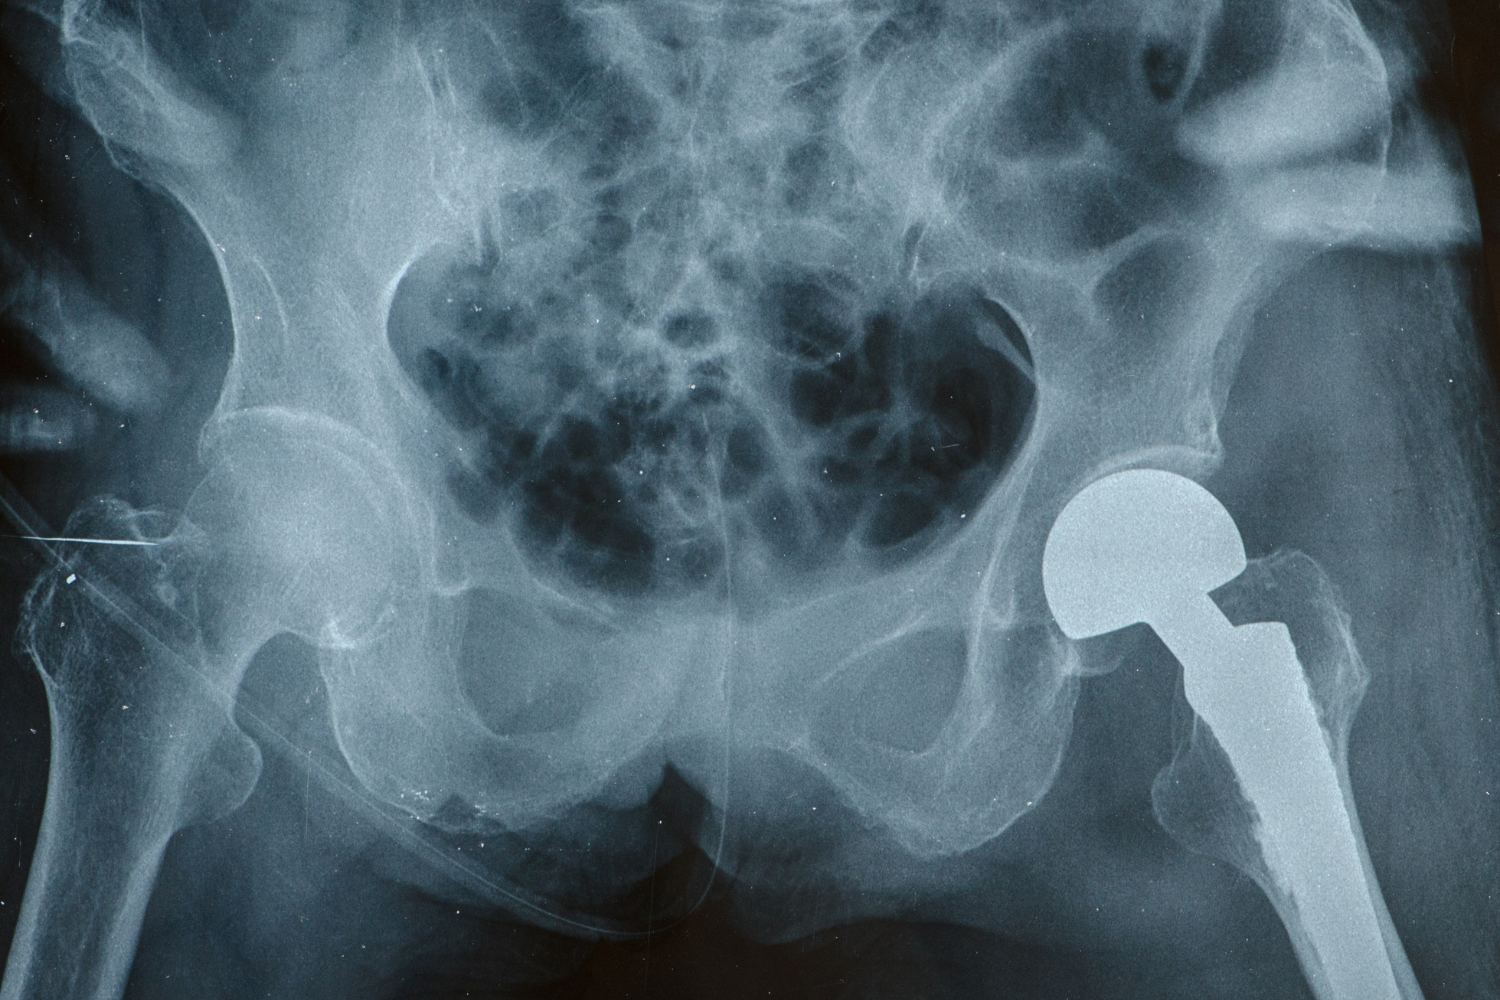

La elección entre la fisioterapia y la artroplastia de cadera depende de la causa y la gravedad del dolor de cadera. Con la orientación experta del Dr. Mangino, puede tomar una decisión segura e informada y dar el primer paso hacia un alivio duradero.

La recuperación de la artroplastia de cadera avanza en etapas estables y manejables, desde la movilidad temprana hasta la independencia total. Bajo la guía experta del Dr. Mangino, los pacientes recuperan la fuerza, la comodidad y la libertad de vivir una vida sin dolor.